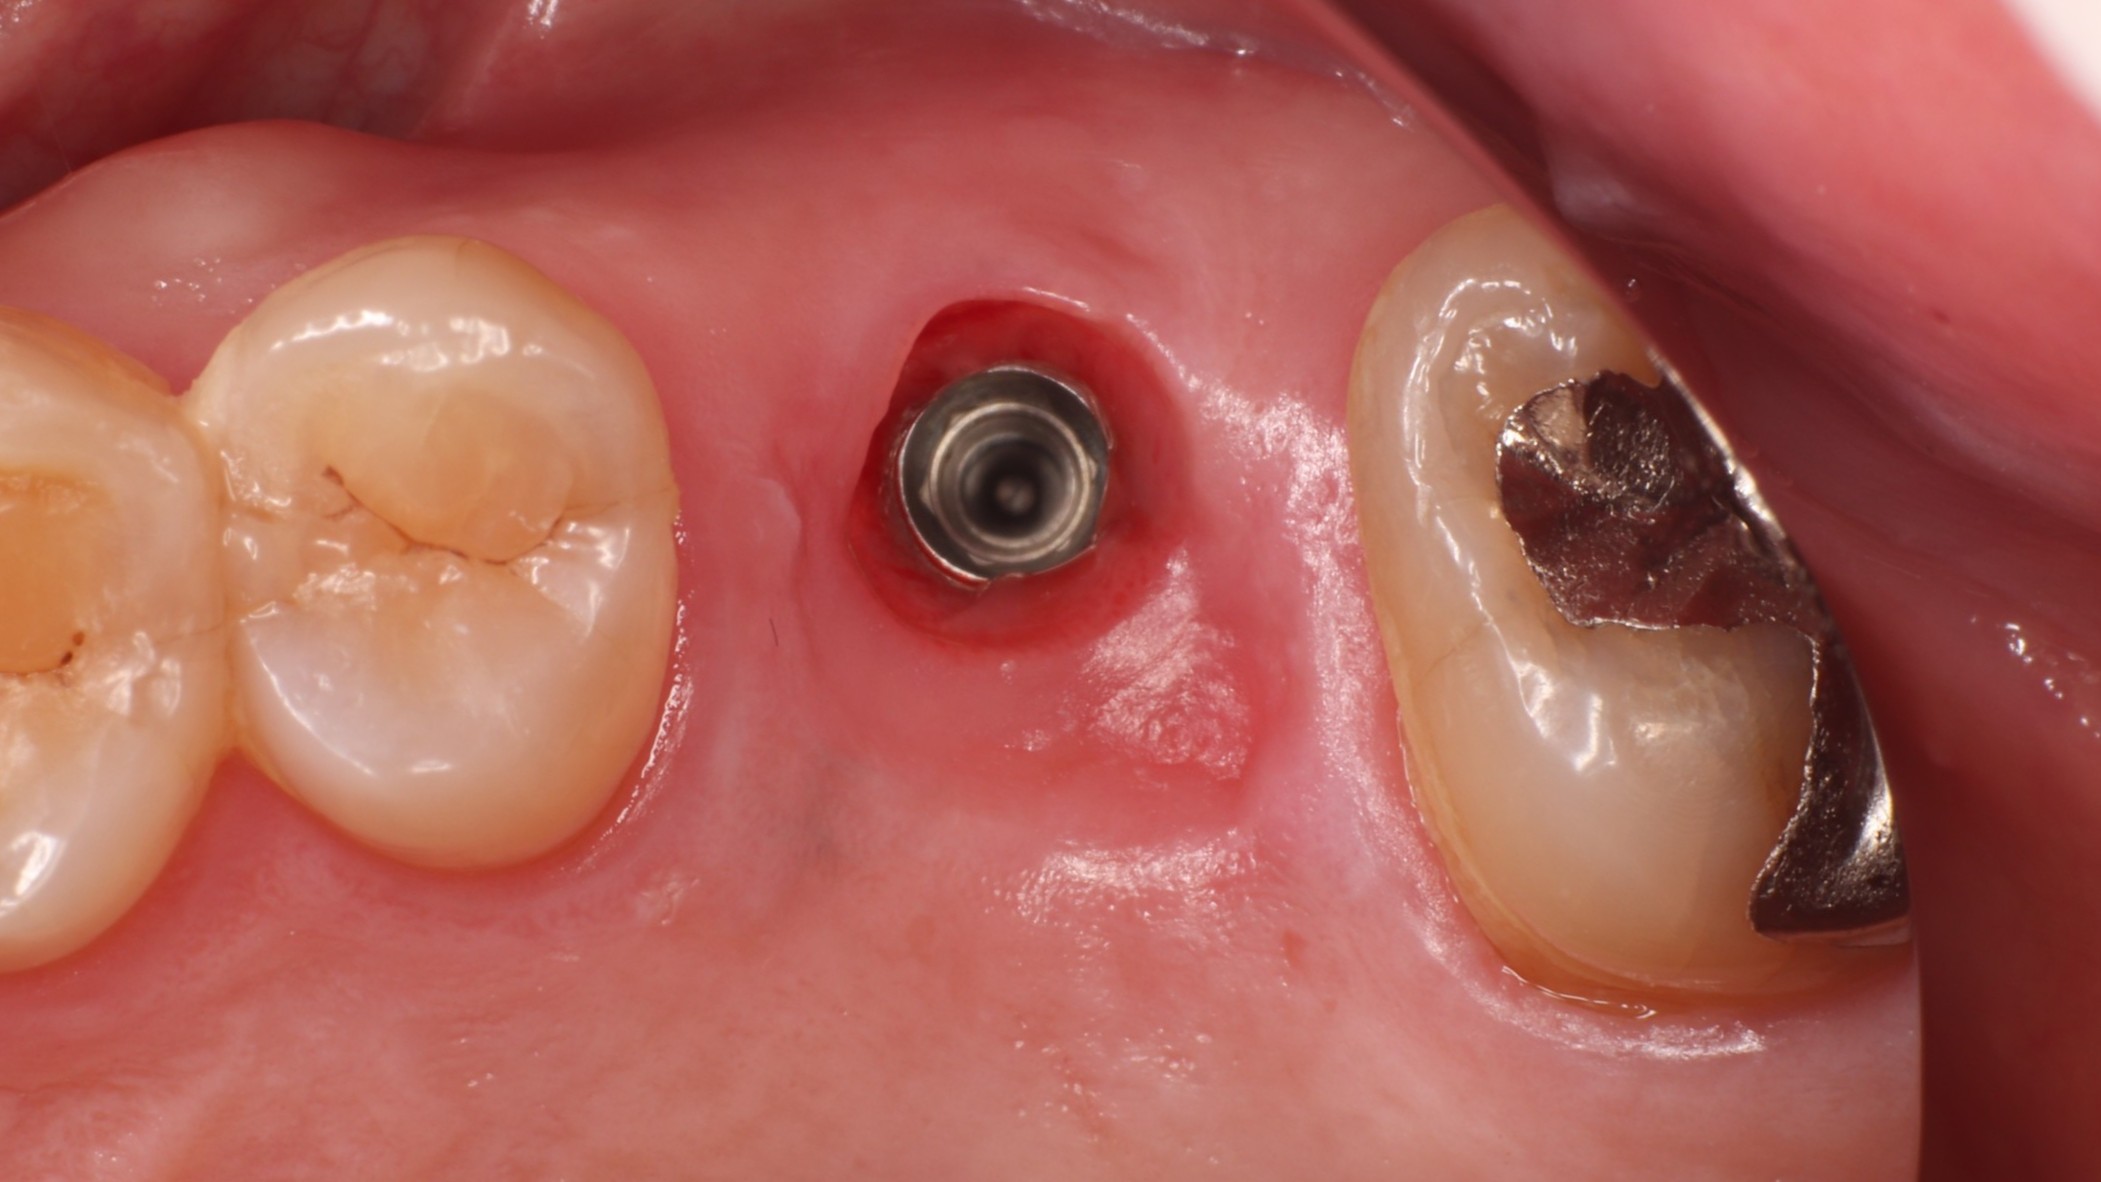

Step 4 治癒期(約3ヶ月)

ヒーリングアバットメント装着中

ヒーリングアバットメントを装着し、歯肉の形態を整えながら待機。インプラントと骨がしっかり結合(オッセオインテグレーション)する期間です。歯肉の状態も良好に経過しました。